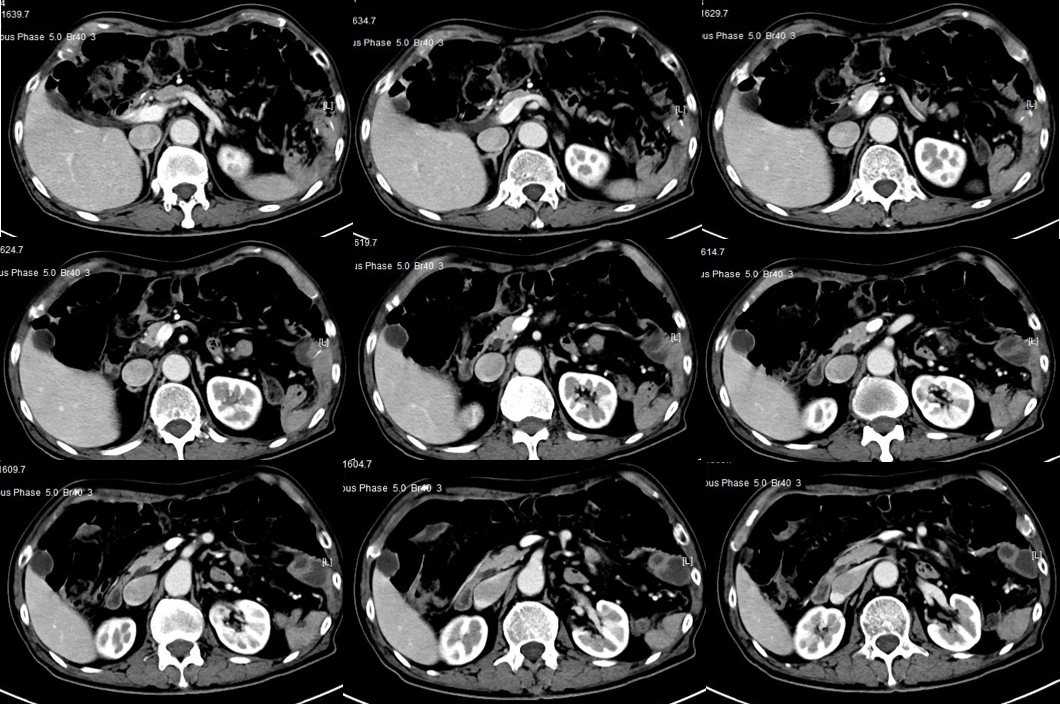

(4)2019-07-24复查CT:腹腔肿大淋巴结较放疗前缩小

(5)2019-09-26复查CT:腹腔肿大淋巴结较放疗后增大,出现左上腹痛

(9)12-19复查CT:腹腔淋巴结较09-26日缩小,3疗程“雷替曲塞 durvalumab“治疗评估达PR。